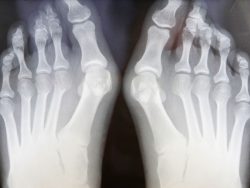

Экзостоз можно выявить во время осмотра и ощупывания подозрительных участков на стопе, голени, руке, ключицах. Недуг развивается постепенно и может никак себя не проявлять в течение долгого времени. Болевые ощущения могут появиться лишь тогда, когда нарост будет давить на ближайший сосуд или нерв. Иногда костяные и хрящевые наросты обнаруживаются случайно, во время рентгена. Рентгеновское обследование дает развернутую информацию о виде и форме нароста, о его размерах степени развития. Нужно помнить, что на снимке рентгена хрящевой ткани новообразования не видно. Из-за этого нарост на фото всегда меньше, нежели в реальности.